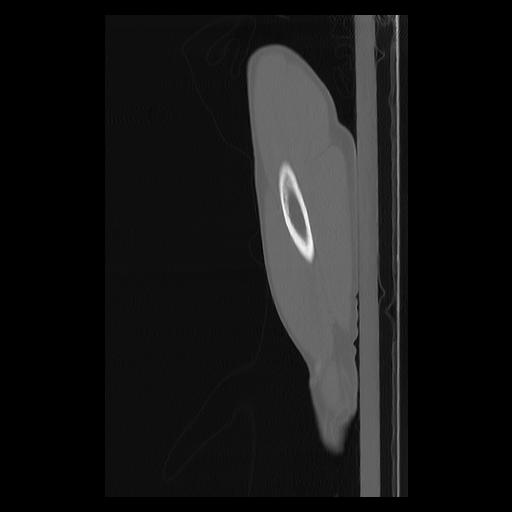

33 PULMON,CE,Sagittal,3.000,PULMON,Sagittal,